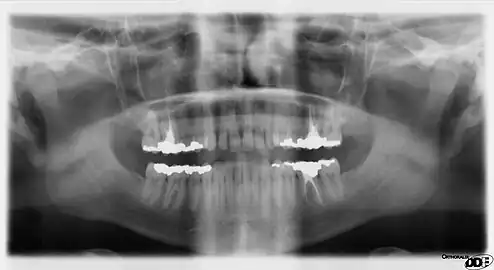

A panoramic radiograph is a panoramic scanning dental X-ray of the upper and lower jaw. It shows a two-dimensional view of a half-circle from ear to ear. Panoramic radiography is a form of focal plane tomography; thus, images of multiple planes are taken to make up the composite panoramic image, where the maxilla and mandible are in the focal trough and the structures that are superficial and deep to the trough are blurred.